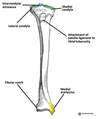

Grey Turner’s sign

Flank ecchymosis

Acute pancreatitis